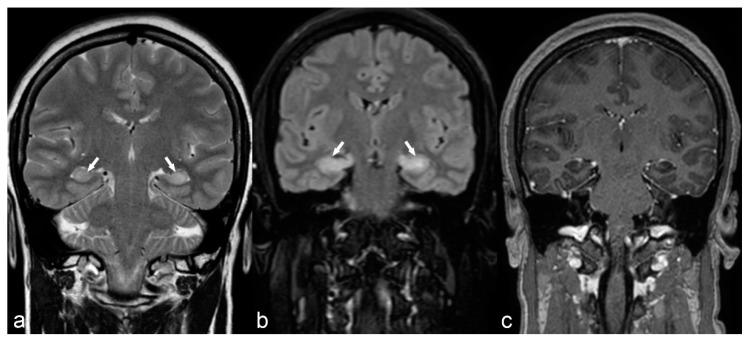

The etiology of epilepsy is variable and sometimes multifactorial. Clinical course and response to treatment largely depend on the precise etiology of the seizures. Along with the electroencephalogram (EEG), neuroimaging techniques, in particular, magnetic resonance imaging (MRI), are the most important tools for determining the possible etiology of epilepsy. Over the last few years, there have been many developments in data acquisition and analysis for both morphological and functional neuroimaging of people suffering from this condition. These innovations have increased the detection of underlying structural pathologies, which have till recently been classified as "cryptogenic" epilepsy. Cryptogenic epilepsy is often refractory to anti-epileptic drug treatment. In drug-resistant patients with structural or consistent functional lesions related to the epilepsy syndrome, surgery is the only treatment that can offer a seizure-free outcome. The pre-operative detection of the underlying structural condition increases the odds of successful surgical treatment of pharmacoresistant epilepsy. This article provides a comprehensive overview of neuroimaging techniques in epilepsy, highlighting recent advances and innovations and summarizes frequent etiologies of epilepsy in order to improve the diagnosis and management of patients suffering from seizures, especially young patients and children.